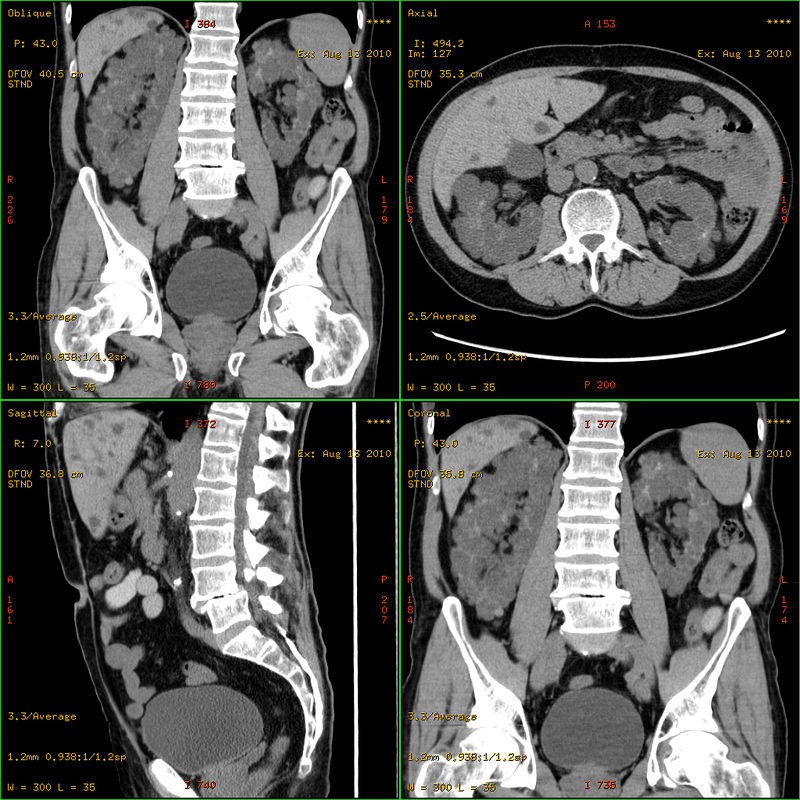

Congenital Horseshoe Kidney. Axial CT image of the abdomen showing a horseshoe kidney. Hellerhoff. Not altered. CC BY-SA 3.0